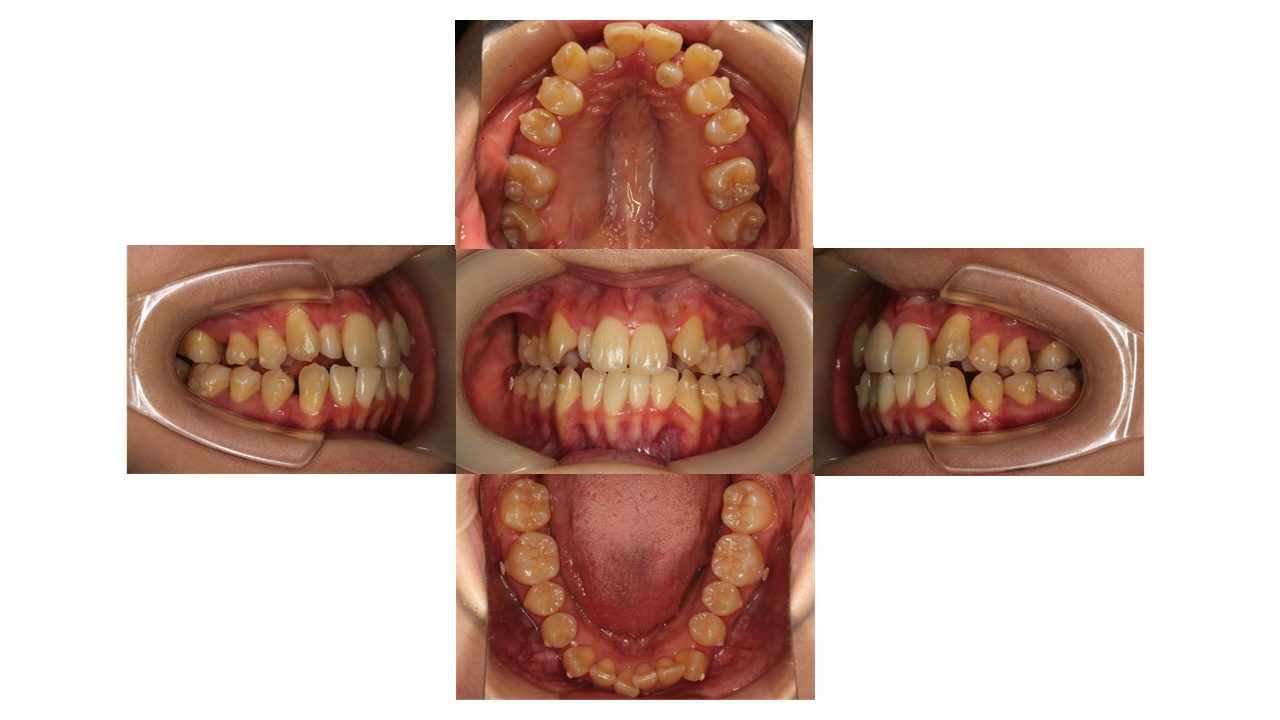

9ヵ月経過の口腔内の状態です。

歯の表面には、「アタッチメント」とよばれる突起が付いています。

アタッチメントには、歯とマウスピースのフィットを良くし、歯の動きを助ける役割があります。